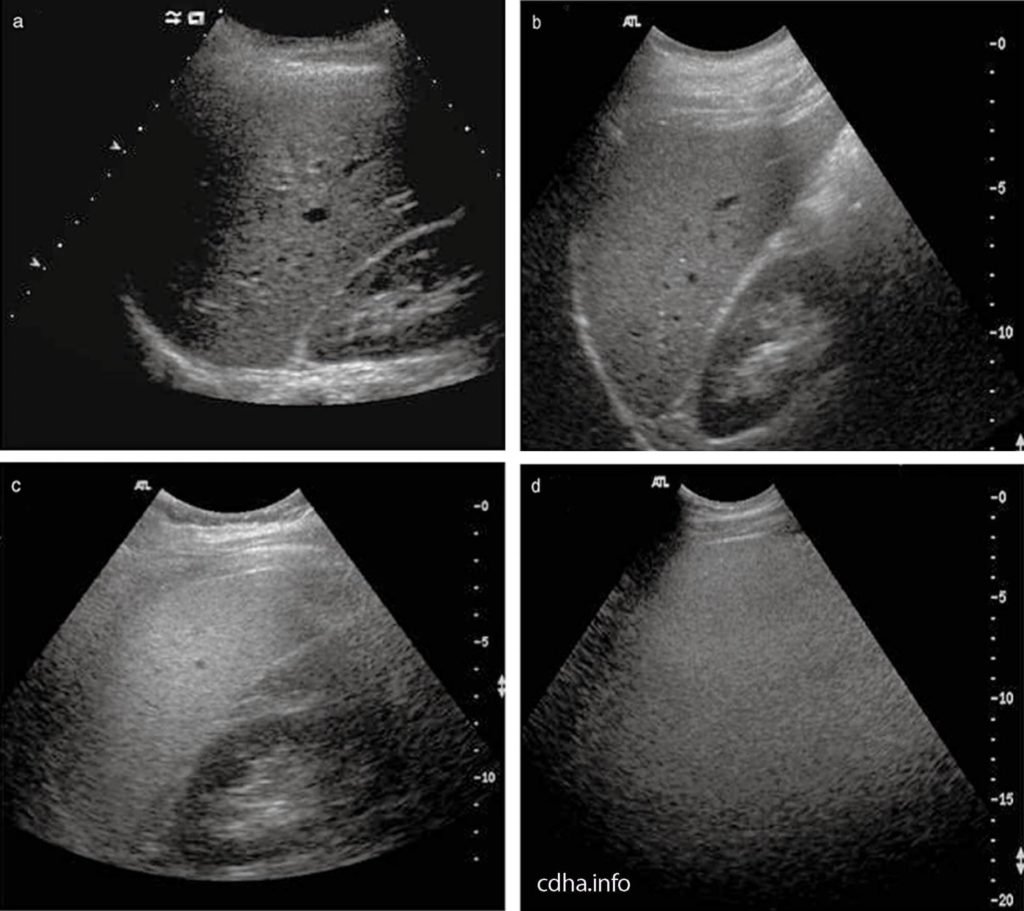

Bệnh gan nhiễm mỡ được phát hiện trên siêu âm chủ yếu dựa vào các triệu chứng như tăng độ sáng tại các vùng khác nhau của gan hoặc tăng độ sáng của mô gan khiến cho đường bờ của các cấu trúc mạch máu bị mờ đi.

Trên hình ảnh siêu âm, hình thái gan sẽ xuất hiện những đốm sáng rải rác hoặc tập trung thành từng khu. Tình trạng này sẽ có sự khác nhau tùy theo mức độ nhiễm mỡ gan ở từng người. Khi gan bị nhiễm mỡ, bác sĩ siêu âm sẽ không nhìn thấy hoặc thấy không rõ hệ thống mạch bên ngoài trên gan.

Bên cạnh đó, độ hồi âm của gan bình thường bằng hoặc tăng nhẹ so với vỏ thận hoặc lách. Khi gan bị nhiễm mỡ, hồi âm của gan sẽ vượt trội so với vỏ thận và lách, đồng thời có sự suy giảm của sóng siêu âm, mất sự rõ nét của cơ hoành và phân định nghèo nàn các cấu trúc trong gan.

3.3 Đánh giá mức độ gan nhiễm mỡ trên siêu âm gan nhiễm mỡ

Bác sĩ có thể đánh giá mức độ gan nhiễm mỡ dựa vào hiện tượng tăng độ sáng của nhu mô gan trên hình ảnh siêu âm gan như sau:

Mức độ 1: Gan tăng âm nhẹ, mức độ hút âm chưa có sự thay đổi đáng kể, vẫn còn xác định được cơ hoành và đường bờ các tĩnh mạch trong gan.

Mức độ 2: gia tăng sự lan tỏa độ hồi âm và hút âm, khả năng xác định được bờ các tĩnh mạch trong gan và cơ hoành đã giảm đi nhiều.

Mức độ 3: gia tăng rõ rệt mức độ hồi âm và hút âm, không còn nhận diện được đường bờ các tĩnh mạch trong gan, cơ hoành, một phần nhu mô gan ở phân thùy sau gan phải trên mặt cắt dưới sườn.